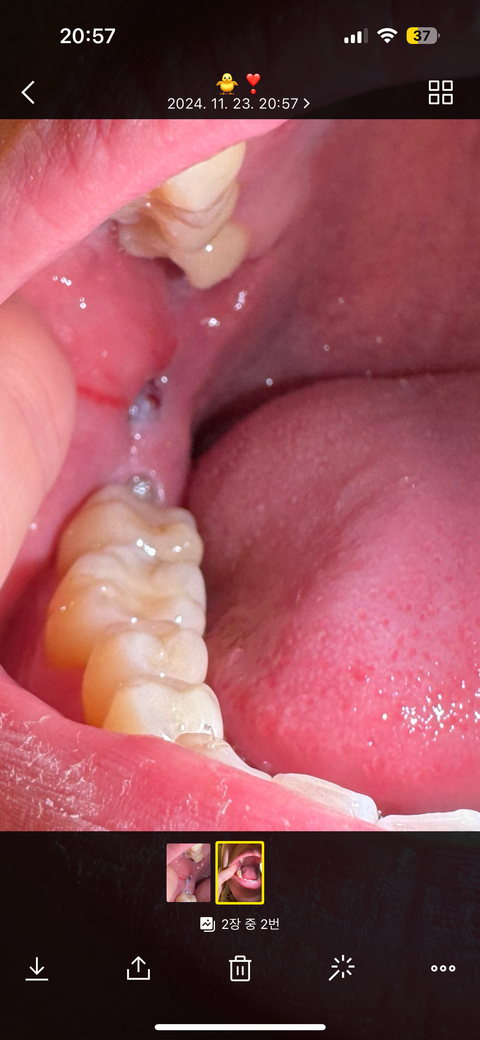

잇몸을 씹었는데 볼쪽 잇몸에 하얀색 이건 뭔가요??

어금니로 볼쪽을 씹었는데 잇몸이 찢어지며 매뵥사랑니 위쪽에 하얀색부분이 나온거 같은데 병명과 치료과정이 궁금합니다

매복사랑니 위쪽 피 중앙에 맺혀있는 부분

• 1번 째 사진

잇몸 씹기로 인해 생긴 손상으로, 잇몸 조직이 부풀거나 하얗게 변색될 수 있습니다. 해당부위 염증이 덧나지 않도록 소독용 헥사메딘 가글액으로 가글을 하여 관리를 하길 권하며, 해당부위가 붓고, 통증이 악화된다면 치과에 방문하여 상태를 확인해보길 권합니다.

별다른 병명이 잇는게 아니라 볼살이 씹히면서 생긴 상처라고 생각하시면됩니다. 그냥 구내염이라고 생각하시면될것같습니다.